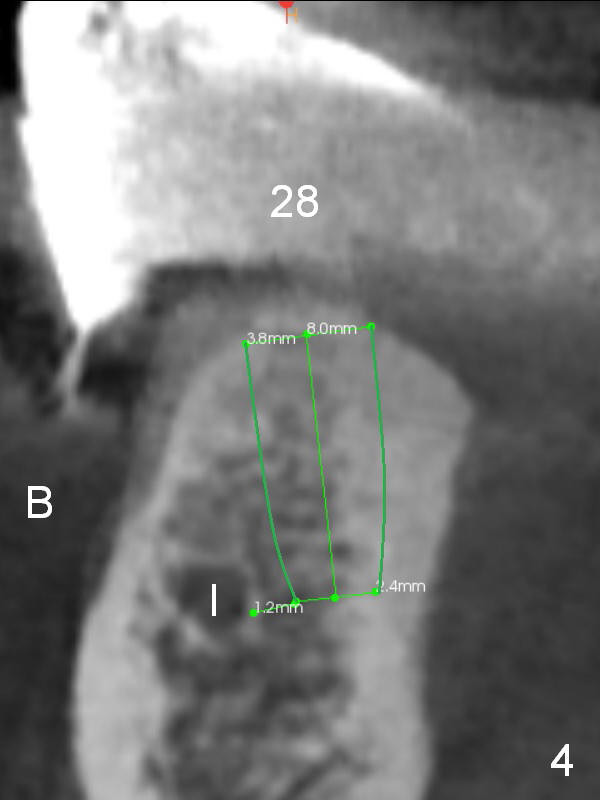

The patient wants to change unstable complete dentures to fixed ones. Because the problem of pain is associated with the lower left (Fig.1 the left Inferior Alveolar Nerve is more superficial), the lower arch will be reconstructed first. Totally 6 implants will be placed for bridges/crowns. Due to time constraint, four implants are placed at the 1st stage (#21, 22, 27 and 28 (Fig.4,5,8,9)); the lower denture will be retained immediately by ball abutments and soft relined. Two to three months later, two more implants will be placed (at #31 and 20, Fig.2,10). Note severe atrophy of the crest at #18 and 19 (Fig.11 and 12). If primary stability is achieved, a fixed immediate provisional will be fabricated.

In contrast to the upper arch, the bone density in the lower arch is high. The challenge is bone height. Short implants will be used (6 mm for #31 (Fig.2) and 8 mm for the majority of the others (at premolar and canine sites). If needed, extra implants will be placed at incisor sites (Fig.6,7 (implant can be longer)) and at #29 (Fig.3) . If a site is too small for a 3.8 mm 2-piece implant, a 1-piece one may be placed.